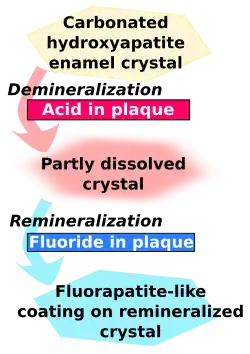

Fluoride exerts its major effect by interfering with the demineralization mechanism of tooth decay. Tooth decay is an infectious disease, the key feature of which is an increase within dental plaque of bacteria such as Streptococcus mutans and Lactobacillus. These produce organic acids when carbohydrates, especially sugar, are eaten.[81] When enough acid is produced to lower the pH below 5.5,[82] the acid dissolves carbonated hydroxyapatite, the main component of tooth enamel, in a process known as demineralization. After the sugar is gone, some of the mineral loss can be recovered—or remineralized—from ions dissolved in the saliva. Cavities result when the rate of demineralization exceeds the rate of remineralization, typically in a process that requires many months or years.[81]

All fluoridation methods, including water fluoridation, create low levels of fluoride ions in saliva and plaque fluid, thus exerting a topical or surface effect. A person living in an area with fluoridated water may experience rises of fluoride concentration in saliva to about 0.04 mg/L several times during a day.[3] Technically, this fluoride does not prevent cavities but rather controls the rate at which they develop.[83] When fluoride ions are present in plaque fluid along with dissolved hydroxyapatite, and the pH is higher than 4.5,[82] a fluorapatite-like remineralized veneer is formed over the remaining surface of the enamel; this veneer is much more acid-resistant than the original hydroxyapatite, and is formed more quickly than ordinary remineralized enamel would be.[81] The cavity-prevention effect of fluoride is mostly due to these surface effects, which occur during and after tooth eruption.[84] Although some systemic (whole-body) fluoride returns to the saliva via blood plasma, and to unerupted teeth via plasma or crypt fluid, there is little data to determine what percentages of fluoride's anticavity effect comes from these systemic mechanisms.[85] Also, although fluoride affects the physiology of dental bacteria,[86] its effect on bacterial growth does not seem to be relevant to cavity prevention.[87]